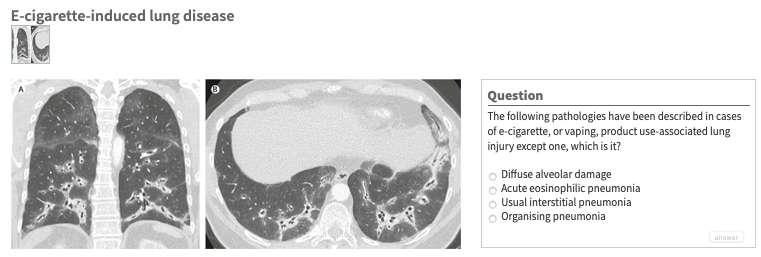

Cue Rossini’s William Tell Overture: “What is….”Click here to answer.#TheLancet #PictureQuiz Share this: Share on X (Opens in new window) X Share on Facebook (Opens in new window) Facebook Like Loading... Published by UBC Abbotsford-Mission Family Practice Residency Program View all posts by UBC Abbotsford-Mission Family Practice Residency Program